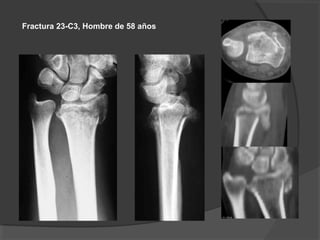

Fractura 23-C3, Hombre de 58 años

Aun en una fractura muy conminuta la

estabilidad que se consigue con una

placa de radio distal es satisfactoria.

A los 16 meses del postoperatorio